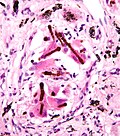

Malignant mesothelioma. H&E stain. | |

Features:[8]

- Infiltrative atypical cells - key feature.

- Infiltration into fat - diagnostic.

- +/-Epithelioid cells - may be cytologically bland, i.e. benign appearing.

- Variable architecture: sheets, microglandular, tubulopapillary.

- +/-Psammoma bodies.

- +/-Spindle cells.

- +/-Ferruginous body - strongly supportive.[9]

- Looks like a (twirling) baton - segemented appearance, brown colour.

- Thin (asbestos) fiber in the core.